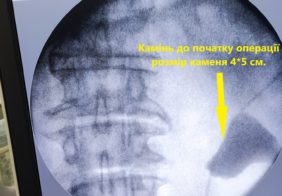

Дроблення коралоподібного каменя через 5 мм. прокол на шкірі

Лікування коралоподібного каменю 1 ступеню право, нирки